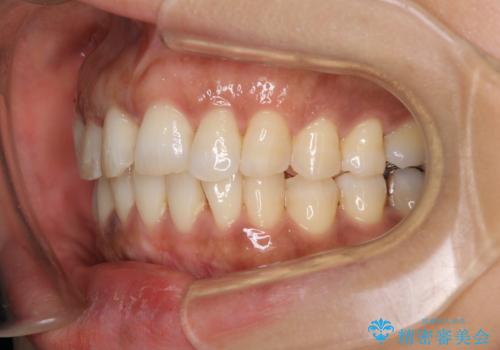

- 40代女性

- インビザライン

- 上下前歯のデコボコ改善をインビザラインにて行いたいとのことで来院された患者様です。

インビザラインをご希望のことで、IPR(歯と歯の間を削る)などによりスペースを獲得して、排列していくこととしました。

骨格的に上下顎が左右にずれていたため、正中位置は現状を維持したまま歯列不正を解消していくことになります。

なかなか装着時間が守れず、後戻りを繰り返しながら治療を進めたため、インビザライン治療期間期限ギリギリの5年弱の期間を要しました。